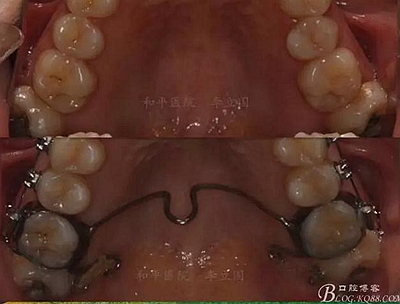

該病例主要為17、27頰側(cè)位同時伴有伸長,當(dāng)然種植支抗可以解決,但還有簡單實用的辦法嗎?如圖,在橫腭桿遠中延伸出牽引鉤,位置盡量遠離合平面,7粘舌側(cè)扣,牽引力的方向為壓低及舌向,下圖為兩個月的效果,17已到位,27還未到位。